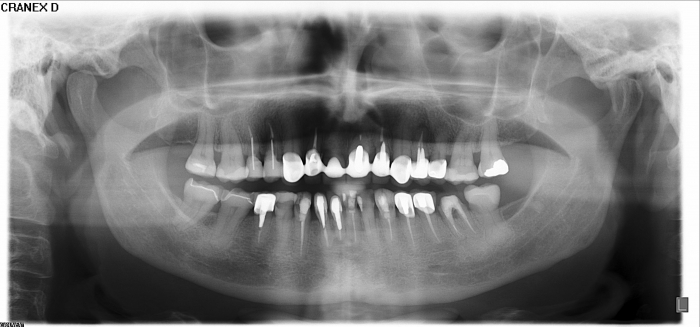

Rx Panorâmico inicial

Rx Panorâmico final 2019